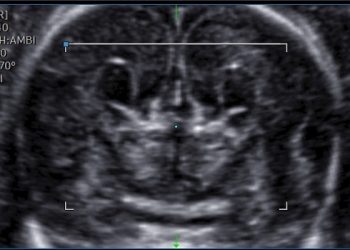

Cari soci, finalmente online le soluzioni dei casi del mese di Giugno!!! Grazie a Valentina D'Ambrosio e Alba Piras!! Caso...